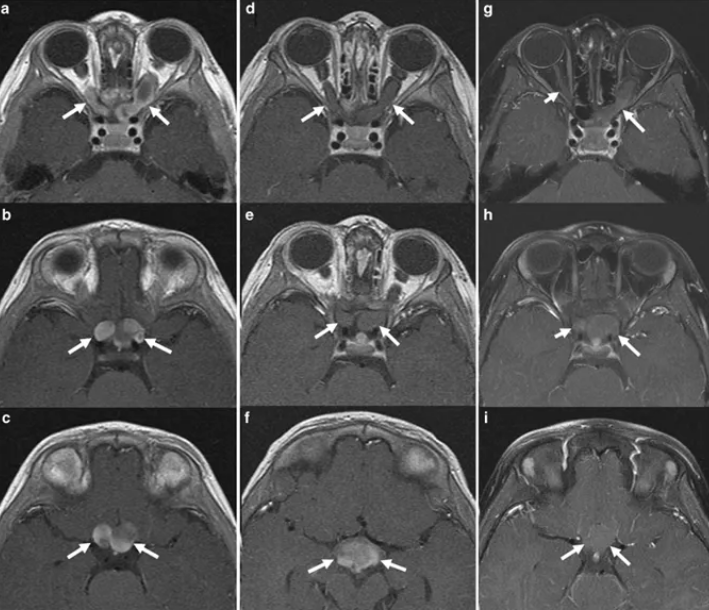

视神经胶质瘤手术前后的影像改变?视神经胶质瘤术前术后的影像改变是医生评估治疗效果和患者康复情况的重要依据。以下将结合磁共振成像(MRI)和计算机...